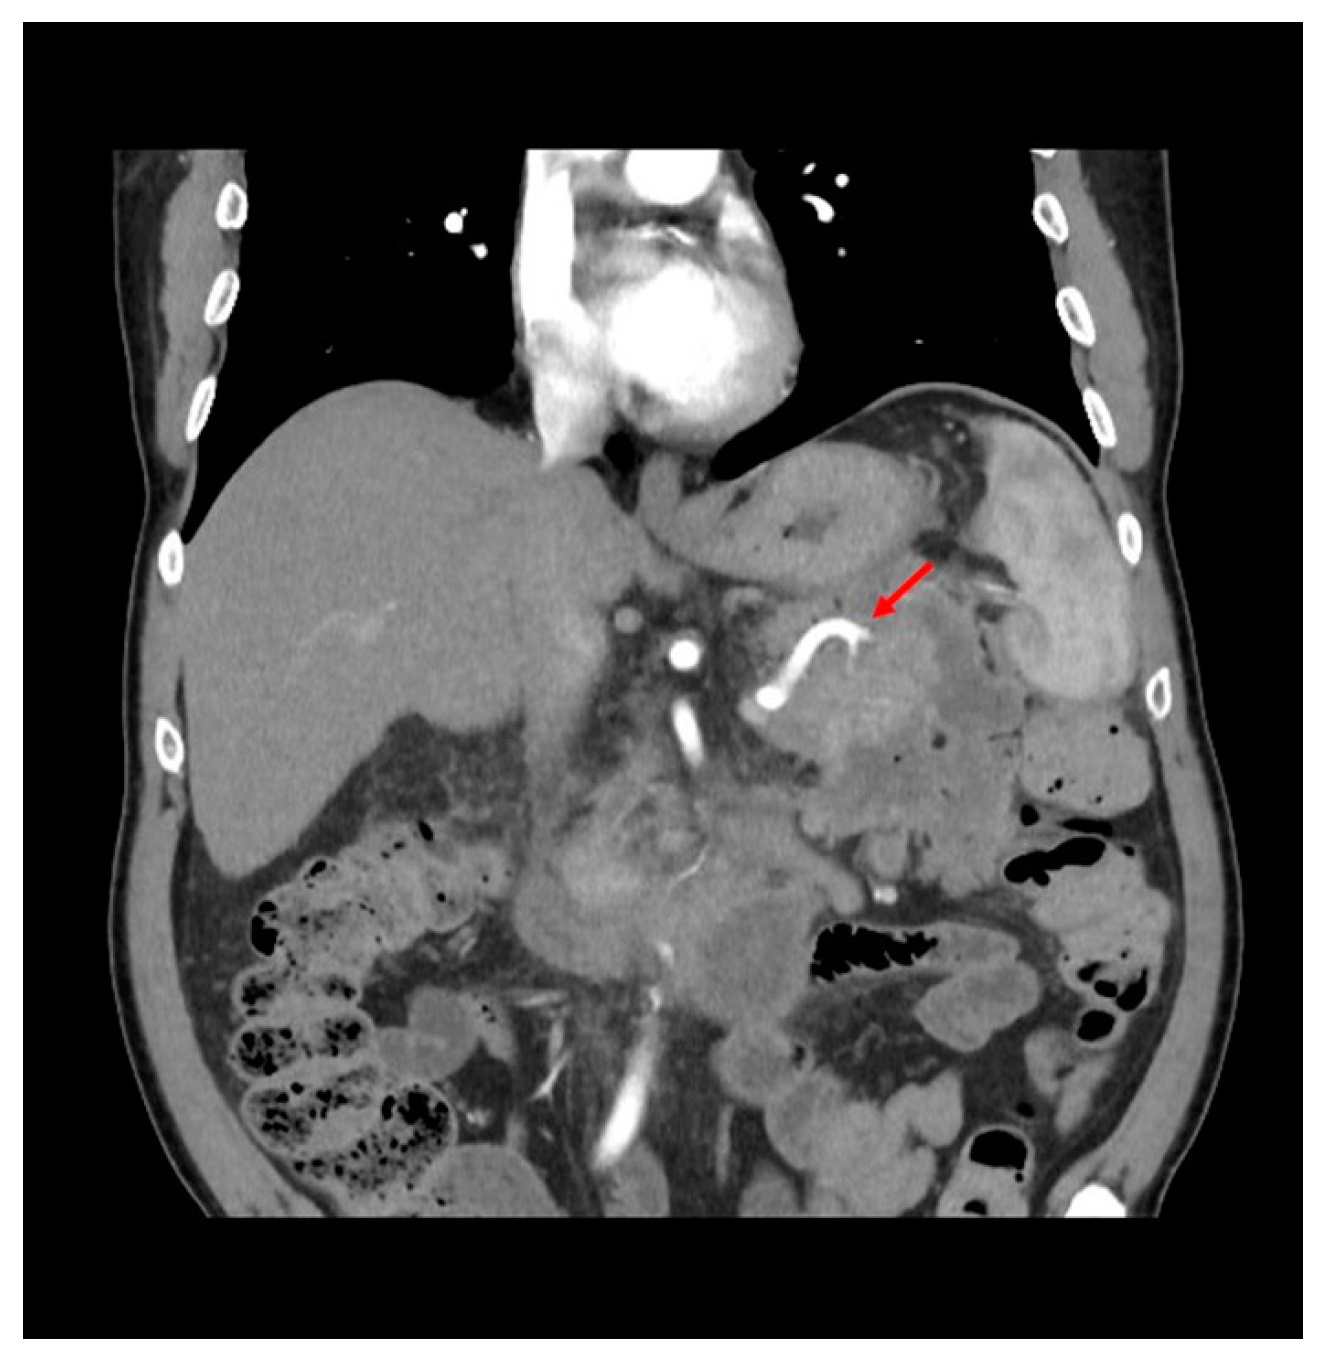

Figure 1.

View of recurrent collection at pre-operative CT-scan. Red arrow points to the splenic artery inside the collection.